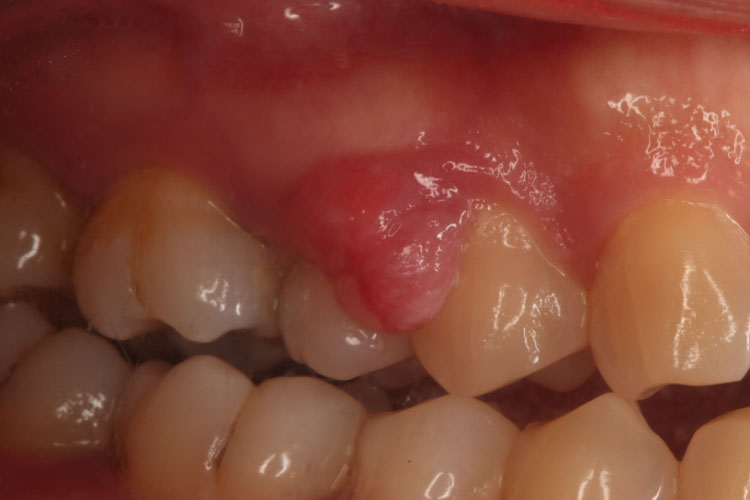

牙龈瘤常发生于中、青年,多发于唇、侧的龈乳头处,舌、腭侧较少见。肿块呈圆球形或椭圆形,大小不一,表面有时呈分叶状。肿块可有蒂,如息肉状,也可无蒂。较大的肿块可被咬破而发生溃疡、出血或伴发感染。